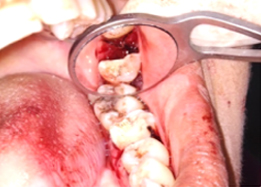

Hemisectomy

Half of Lower molar tooth along with diseased root removed & rest part is saved.